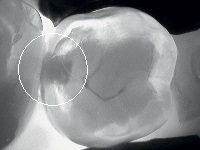

The detection of carious lesions and cracks at an early stage is necessary in order to implement prophylactic, or minimally-invasive and pain-free treatment. In daily practice, the diagnosis of initial lesions is not always simple.

The new KaVo DIAGNOcam is the first camera system that uses the tooth's structure to verify caries diagnosis. To do this, the tooth is transilluminated utilising light of a specific wavelength (780 nm generated by a led laser) and used like a light conductor. A digital video camera records the image and displays it live on a computer screen. Carious lesions are displayed as dark shadows. With its DIFOTI technology (Digital Imaging Fiberoptic Transillumination), DIAGNOcam offers high diagnostic safety which is comparable or superior to X-ray diagnosis in many cases, in particular with regard to approximal and occlusal caries. Furthermore, it is possible to show certain kinds of secondary caries and cracks. The X-ray free device thereby allows early and very gentle caries detection.